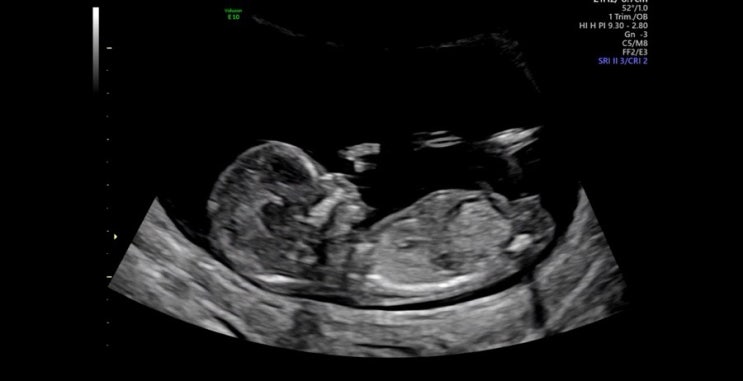

임신 16주차 / 드디어 딱지의 성별을 확인했다

7/17 드디어 딱지의 성별을 알 수 있는 날 두근두근하며 입체초음파를 봤는데 성별은 담당 선생님께 보라고...